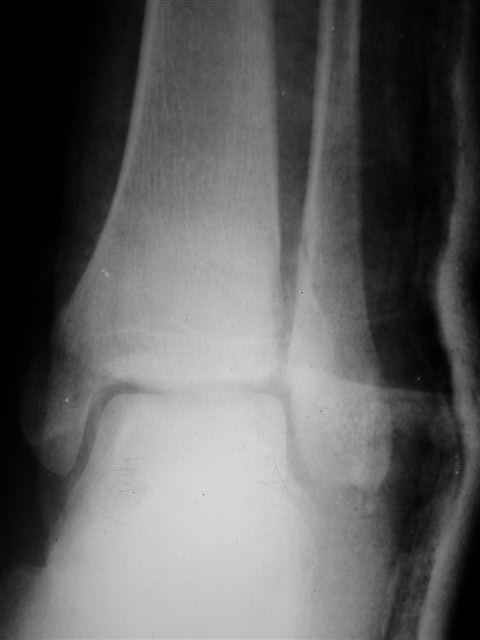

> Если Вас не затруднит, пришлите, пожалуйста, рентгенограммы. Я

> интересуюсь тактикой лечения повреждений голеностопного сустава.

Ничего сверхъестественного, но если есть интерес, то в понедельник пересниму Рг-граммы и отправлю.

Уважаемый Иван,

Я предупреждал, что ничего сверхъестественного. Каюсь, что одна из спиц прошла несколько дальше, чем нужно было, но главное - перелом стабилизирован и больной работает суставом в полном объёме, несмотря на представленную раннее травму коленного сустава.